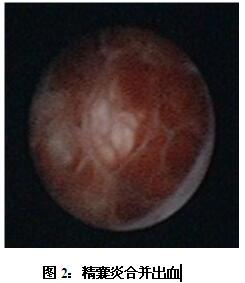

該患者在云南一家三甲醫(yī)院檢查時,發(fā)現(xiàn)雙側(cè)精囊飽滿,質(zhì)地不均勻,考慮精囊炎,經(jīng)輸液抗炎對癥治療血精不愈,患者及家屬極度緊張,他們通過熟人介紹來到我院就診。馬主任經(jīng)過仔細(xì)檢查,配合超聲、CT、MRI,診斷為“精囊炎、精囊結(jié)石”,認(rèn)為通過精囊鏡檢查配合局部沖洗、灌藥、碎石才能達(dá)到根治。在中山三院肖恒軍博士的指導(dǎo)及陳日新副主任醫(yī)師、鄧釗晉副主任醫(yī)師以及麻醉科和手術(shù)室的配合下,馬子芳主任為該患者實施了精囊鏡檢查,發(fā)現(xiàn)患者雙側(cè)精囊內(nèi)充滿結(jié)石和淤積血塊,即予以套石網(wǎng)籃取石和精囊沖洗(如下圖),同時行囊內(nèi)藥物灌注。術(shù)后2天,經(jīng)直腸彩超復(fù)查,精囊恢復(fù)正常形態(tài)大小,術(shù)后4天治愈出院。